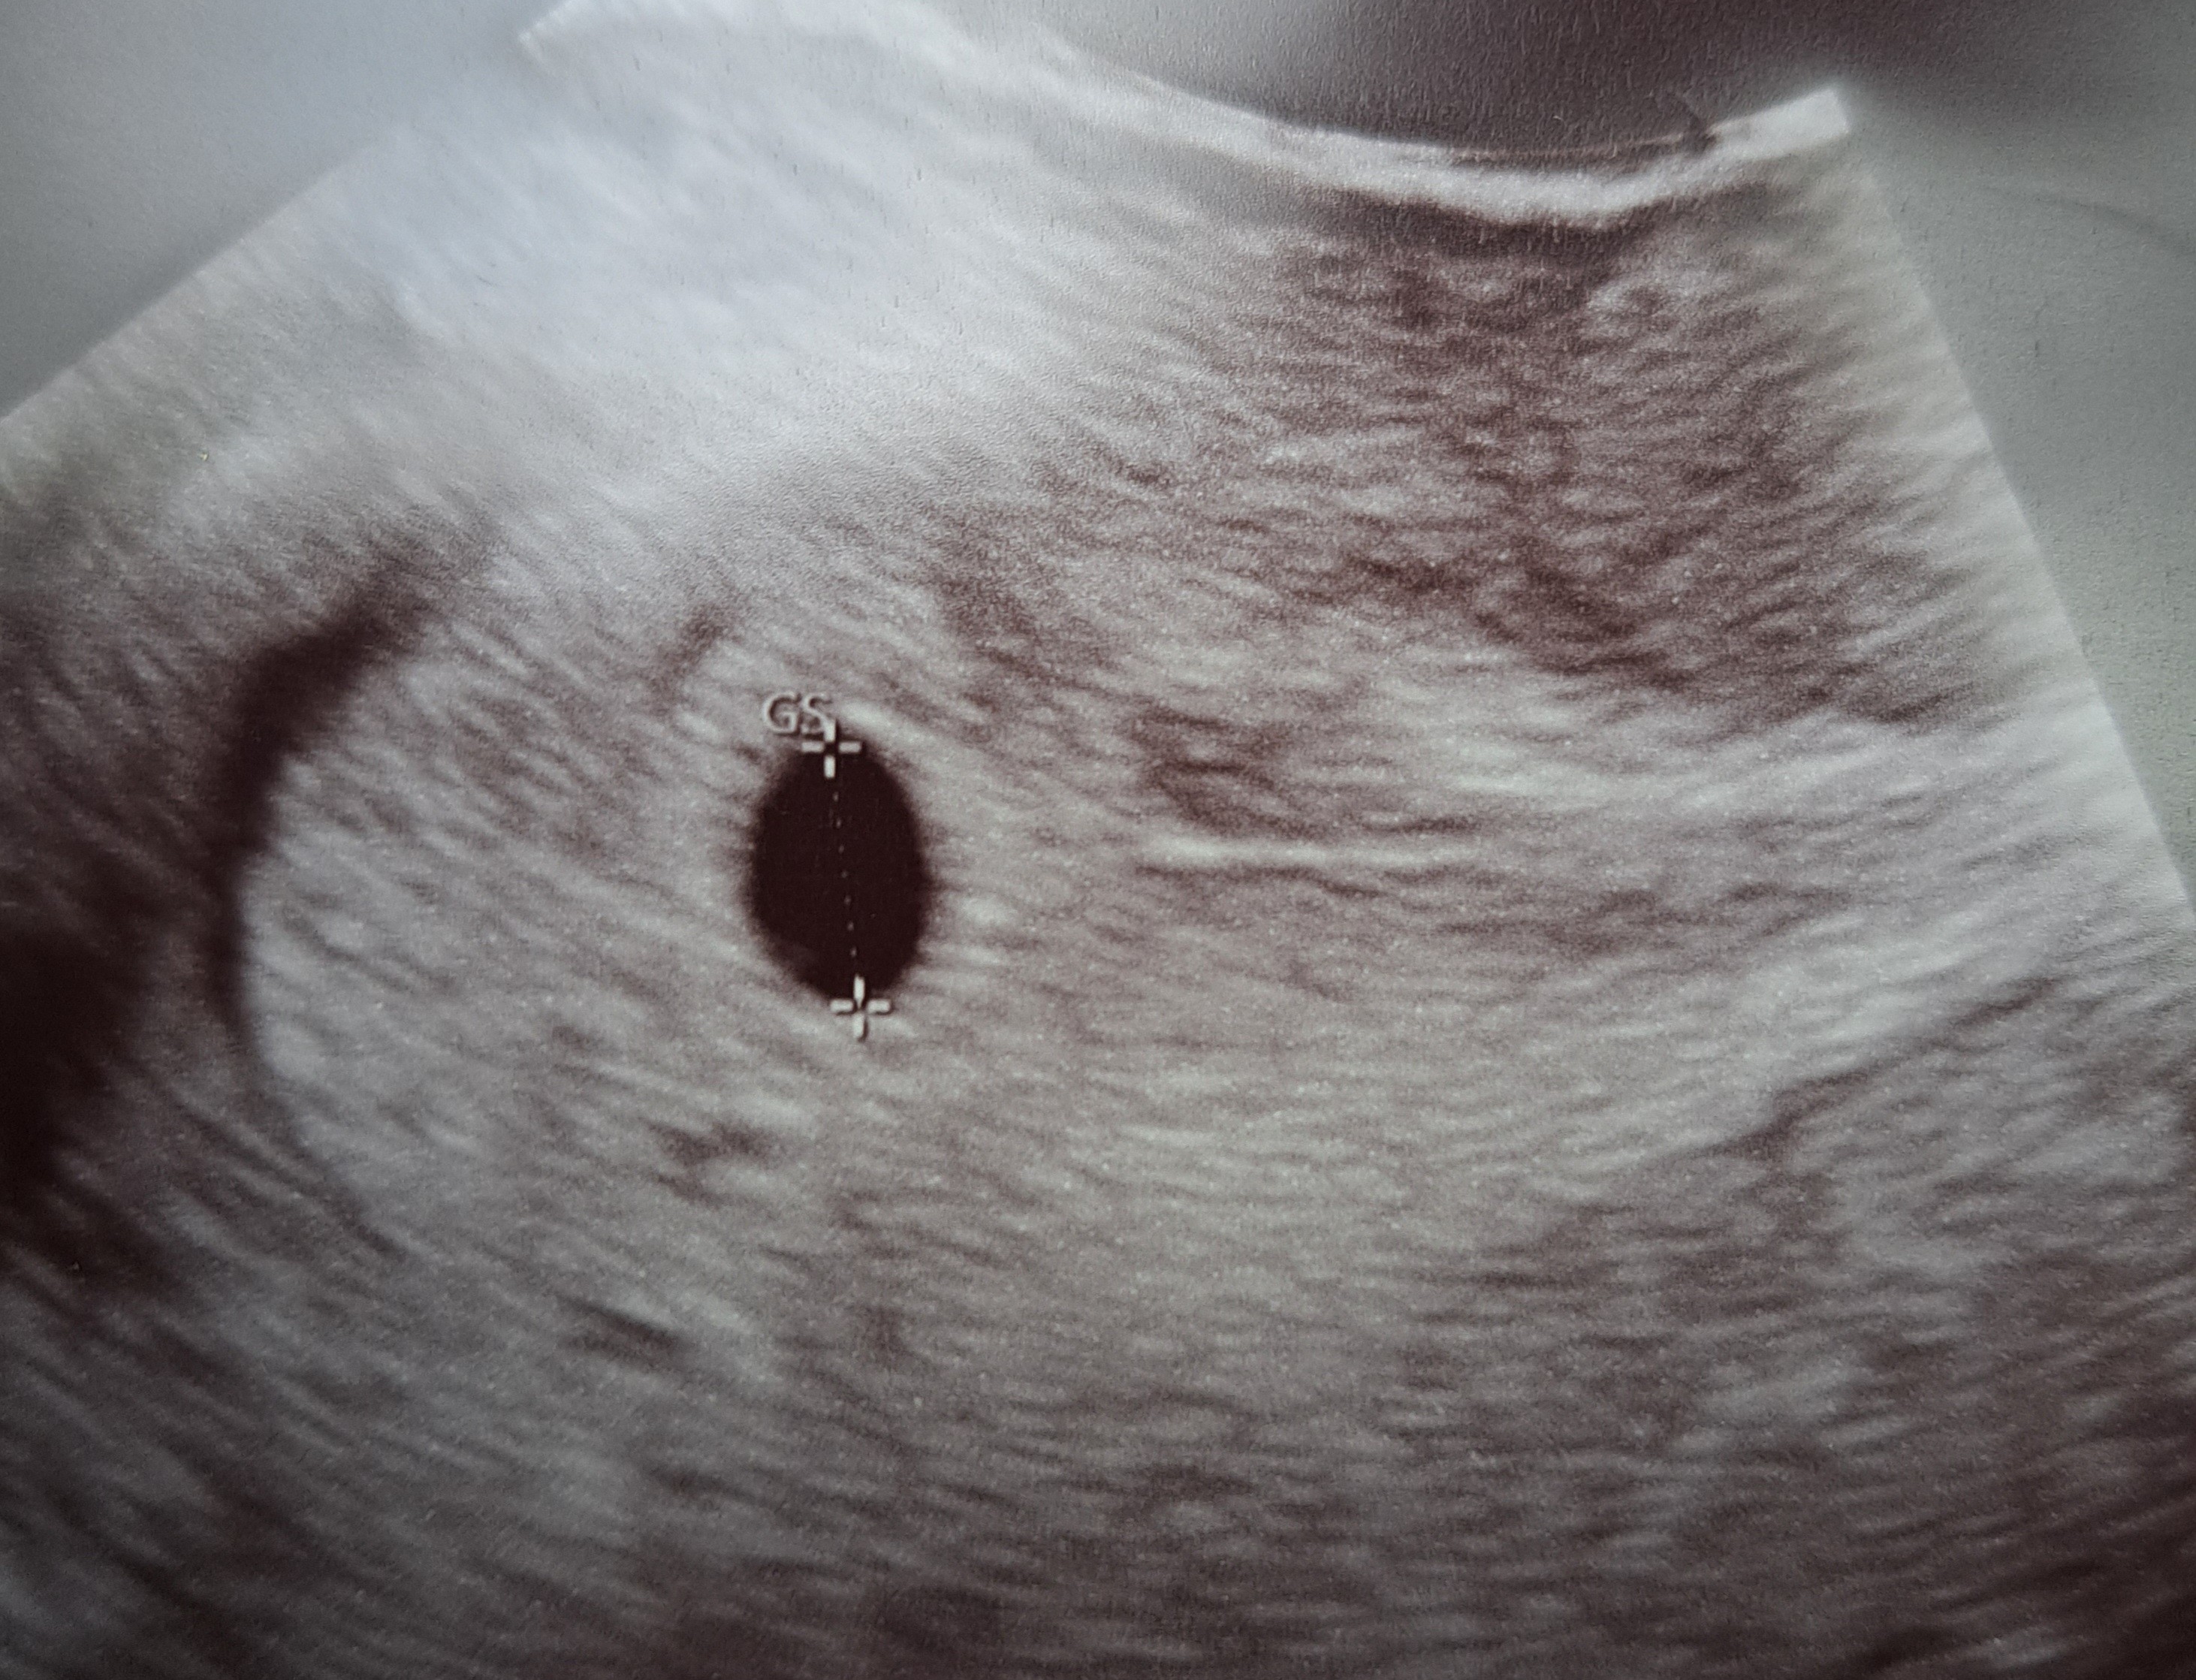

5+4 z tym że ja mam późne owulację 18- 20dcKtóry u Ciebie tc?

To tym bardziej, jak już widać zarodek to super5+4 z tym że ja mam późne owulację 18- 20dc

DziękujęTo tym bardziej, jak już widać zarodek to super![]()